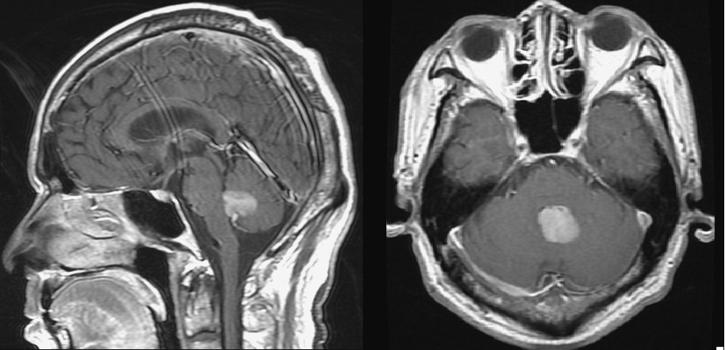

A 61-year-old male presenting with 3 months of headache and dizziness followed with unsteady gait for days. The MR imaging of brain revealed a homogeneously enhancing lesion occupying almost the whole 4th ventricle.The tumor was removed subtotally via suboccipital craniotomy. Histopathology revealed the lesion be a diffuse large B-cell lymphoma.

一名61岁男性,出现3个月的头痛和头晕,随后步态不稳数天。脑部磁共振成像显示一个均匀强化的病变几乎占据整个第四脑室。通过枕下开颅术部分切除肿瘤。组织病理学显示病变为弥漫性大B细胞淋巴瘤。